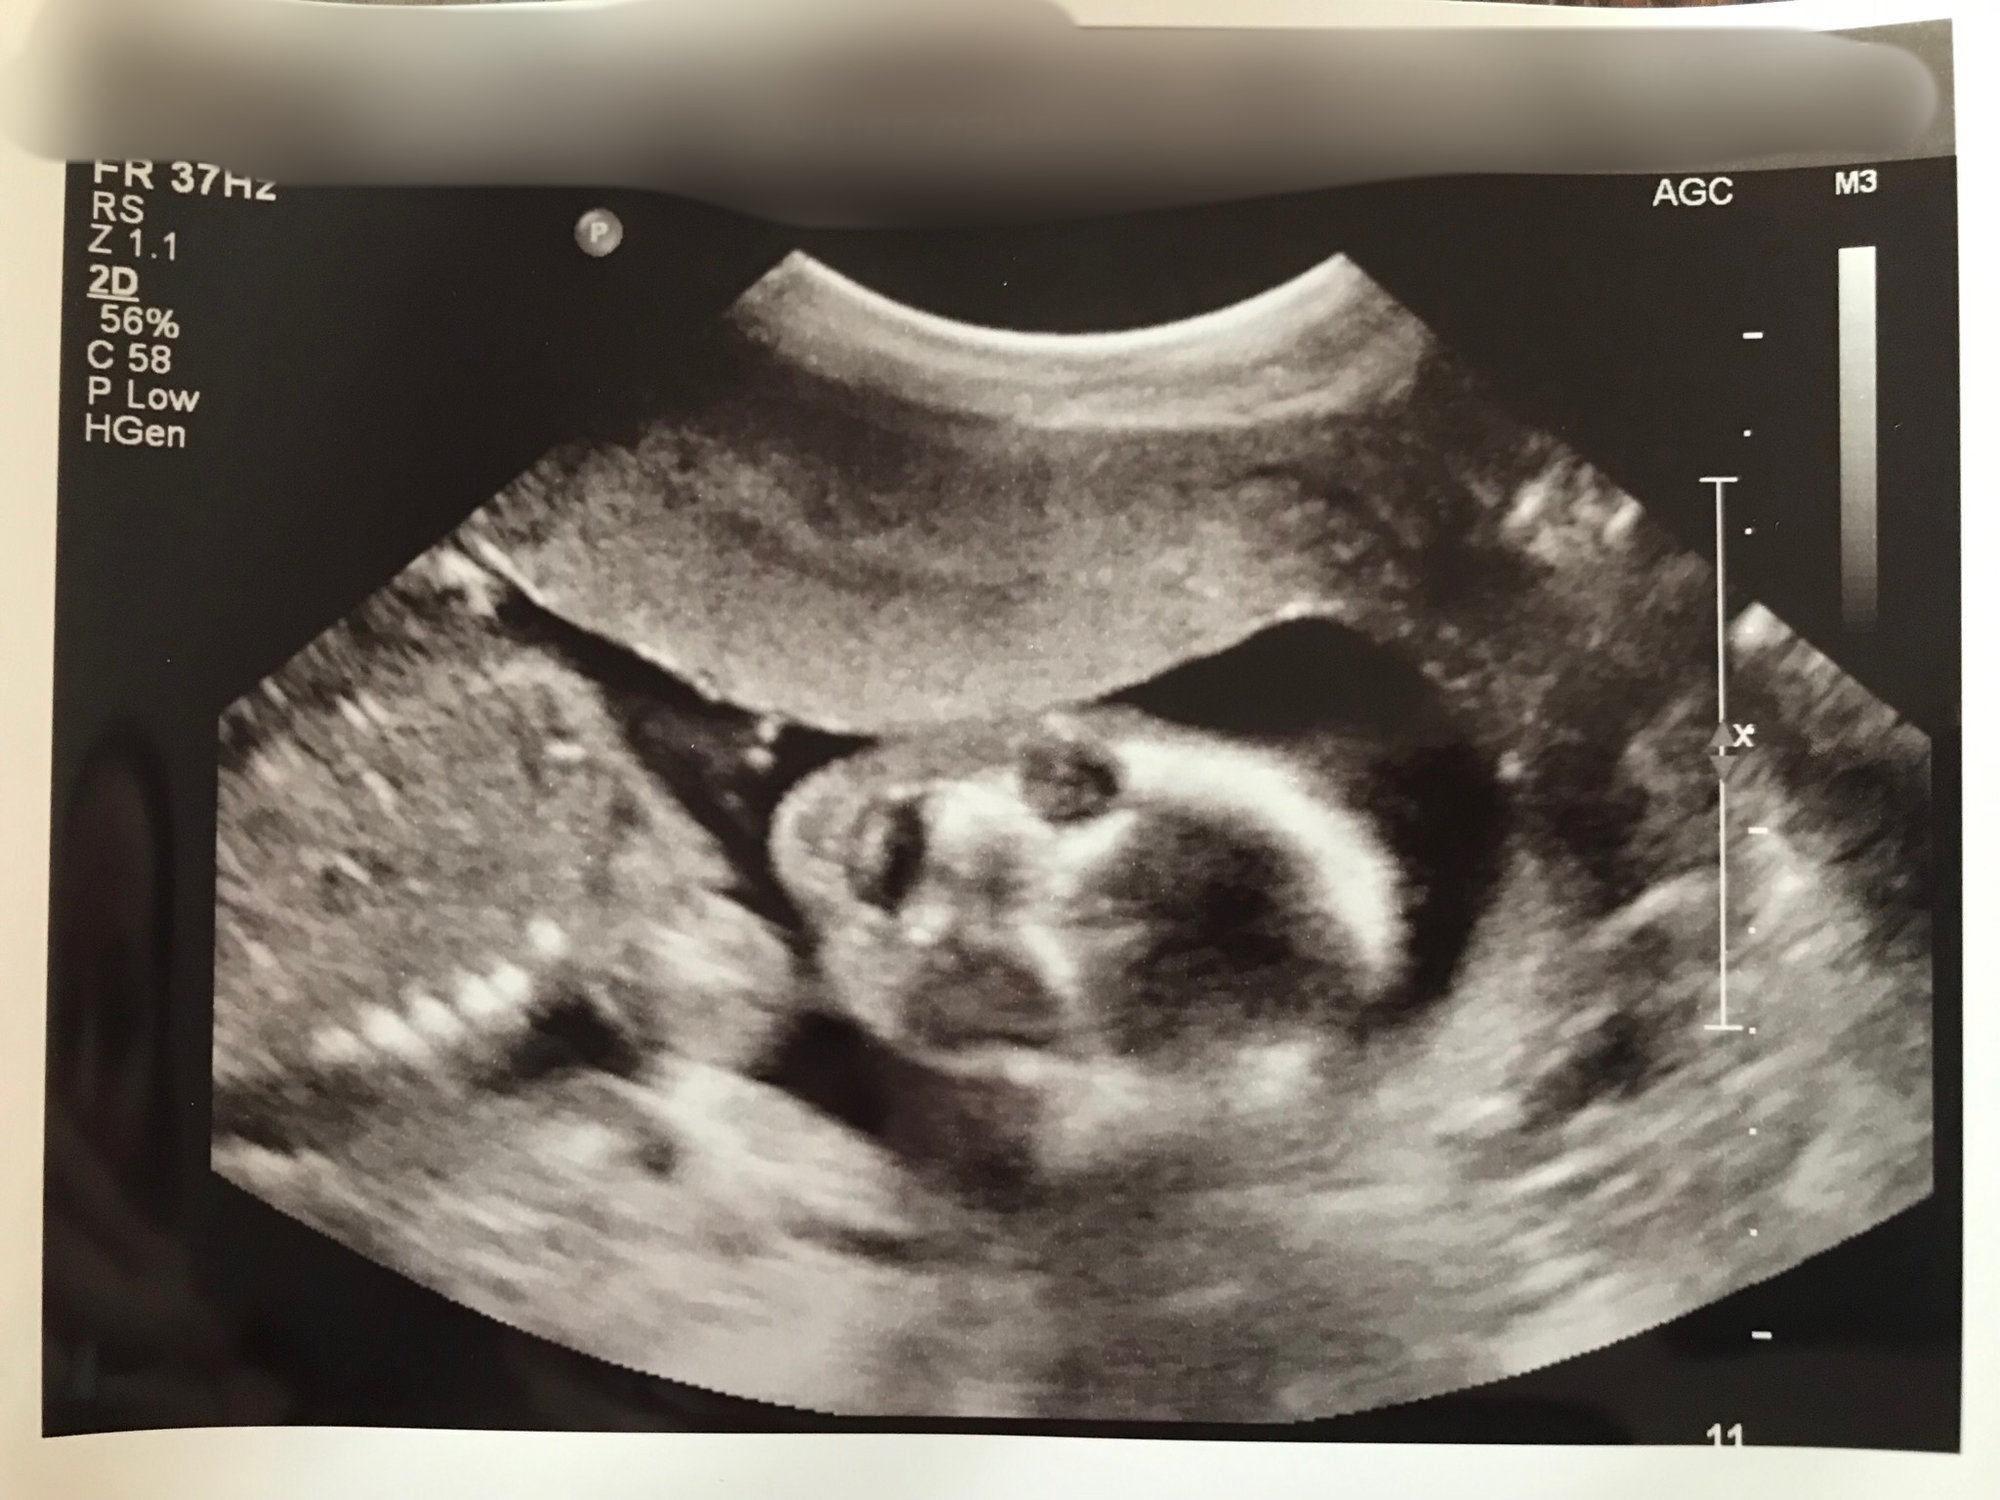

We had our anatomy scan this morning. Turns out baby number three is a boy! Couldn’t be more excited! We got so many great pics but I love this one. It looks a little creepy but when she was trying to get this picture the baby kept opening his mouth and sticking his little tongue out at us. You can even see his tongue in the pic. It was so cute and funny. I already love him so much!!